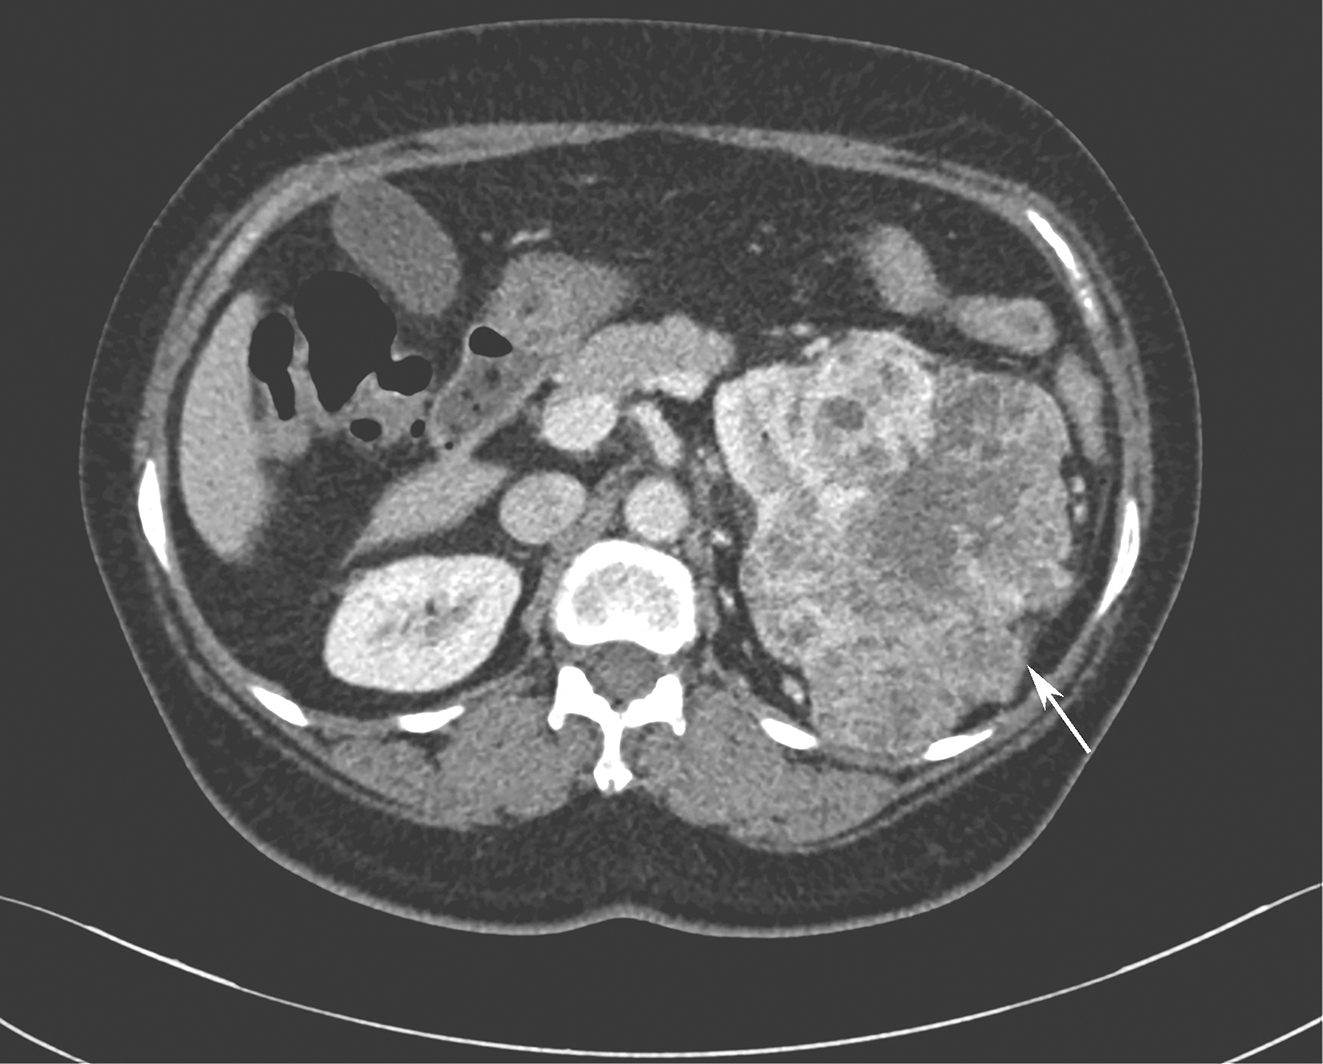

全腹增强CT:①盆腔积液、积血,盆腔软组织密度肿块影,最大截面约15cm×9cm,与子宫分界不清,增强扫描呈明显不均匀强化,内见血管影(图1);②左肾中上份见巨大不规则占位,最大截面约15cm×10cm,内散在点状钙化灶,增强扫描呈明显不均匀强化,左右肾受压下移(图2)。

图2增强CT示左肾占位病变